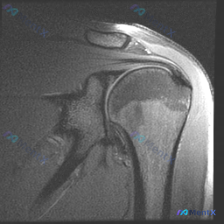

只看肩关节MRI,盂唇真的有问题吗?

看到一个肩关节MRI的病例资料,患者主要关注的是「盂唇病理」,但整理影像信息时发现几个点:

- 冠状位T2加权像上,冈上肌腱靠近肱骨大结节止点处有明显高信号,形态不规则,连续性似有中断

- 肩峰下-三角肌下滑囊可见高信号积液,滑囊略增厚

- 盂唇位置信号未见明显撕裂性高信号

- 肱骨头、肩峰等皮质骨信号完整,骨髓未见弥漫性水肿

先不抛结论,大家只看这些表现,「盂唇病变」的可能性大吗?影像里的核心阳性发现是什么?